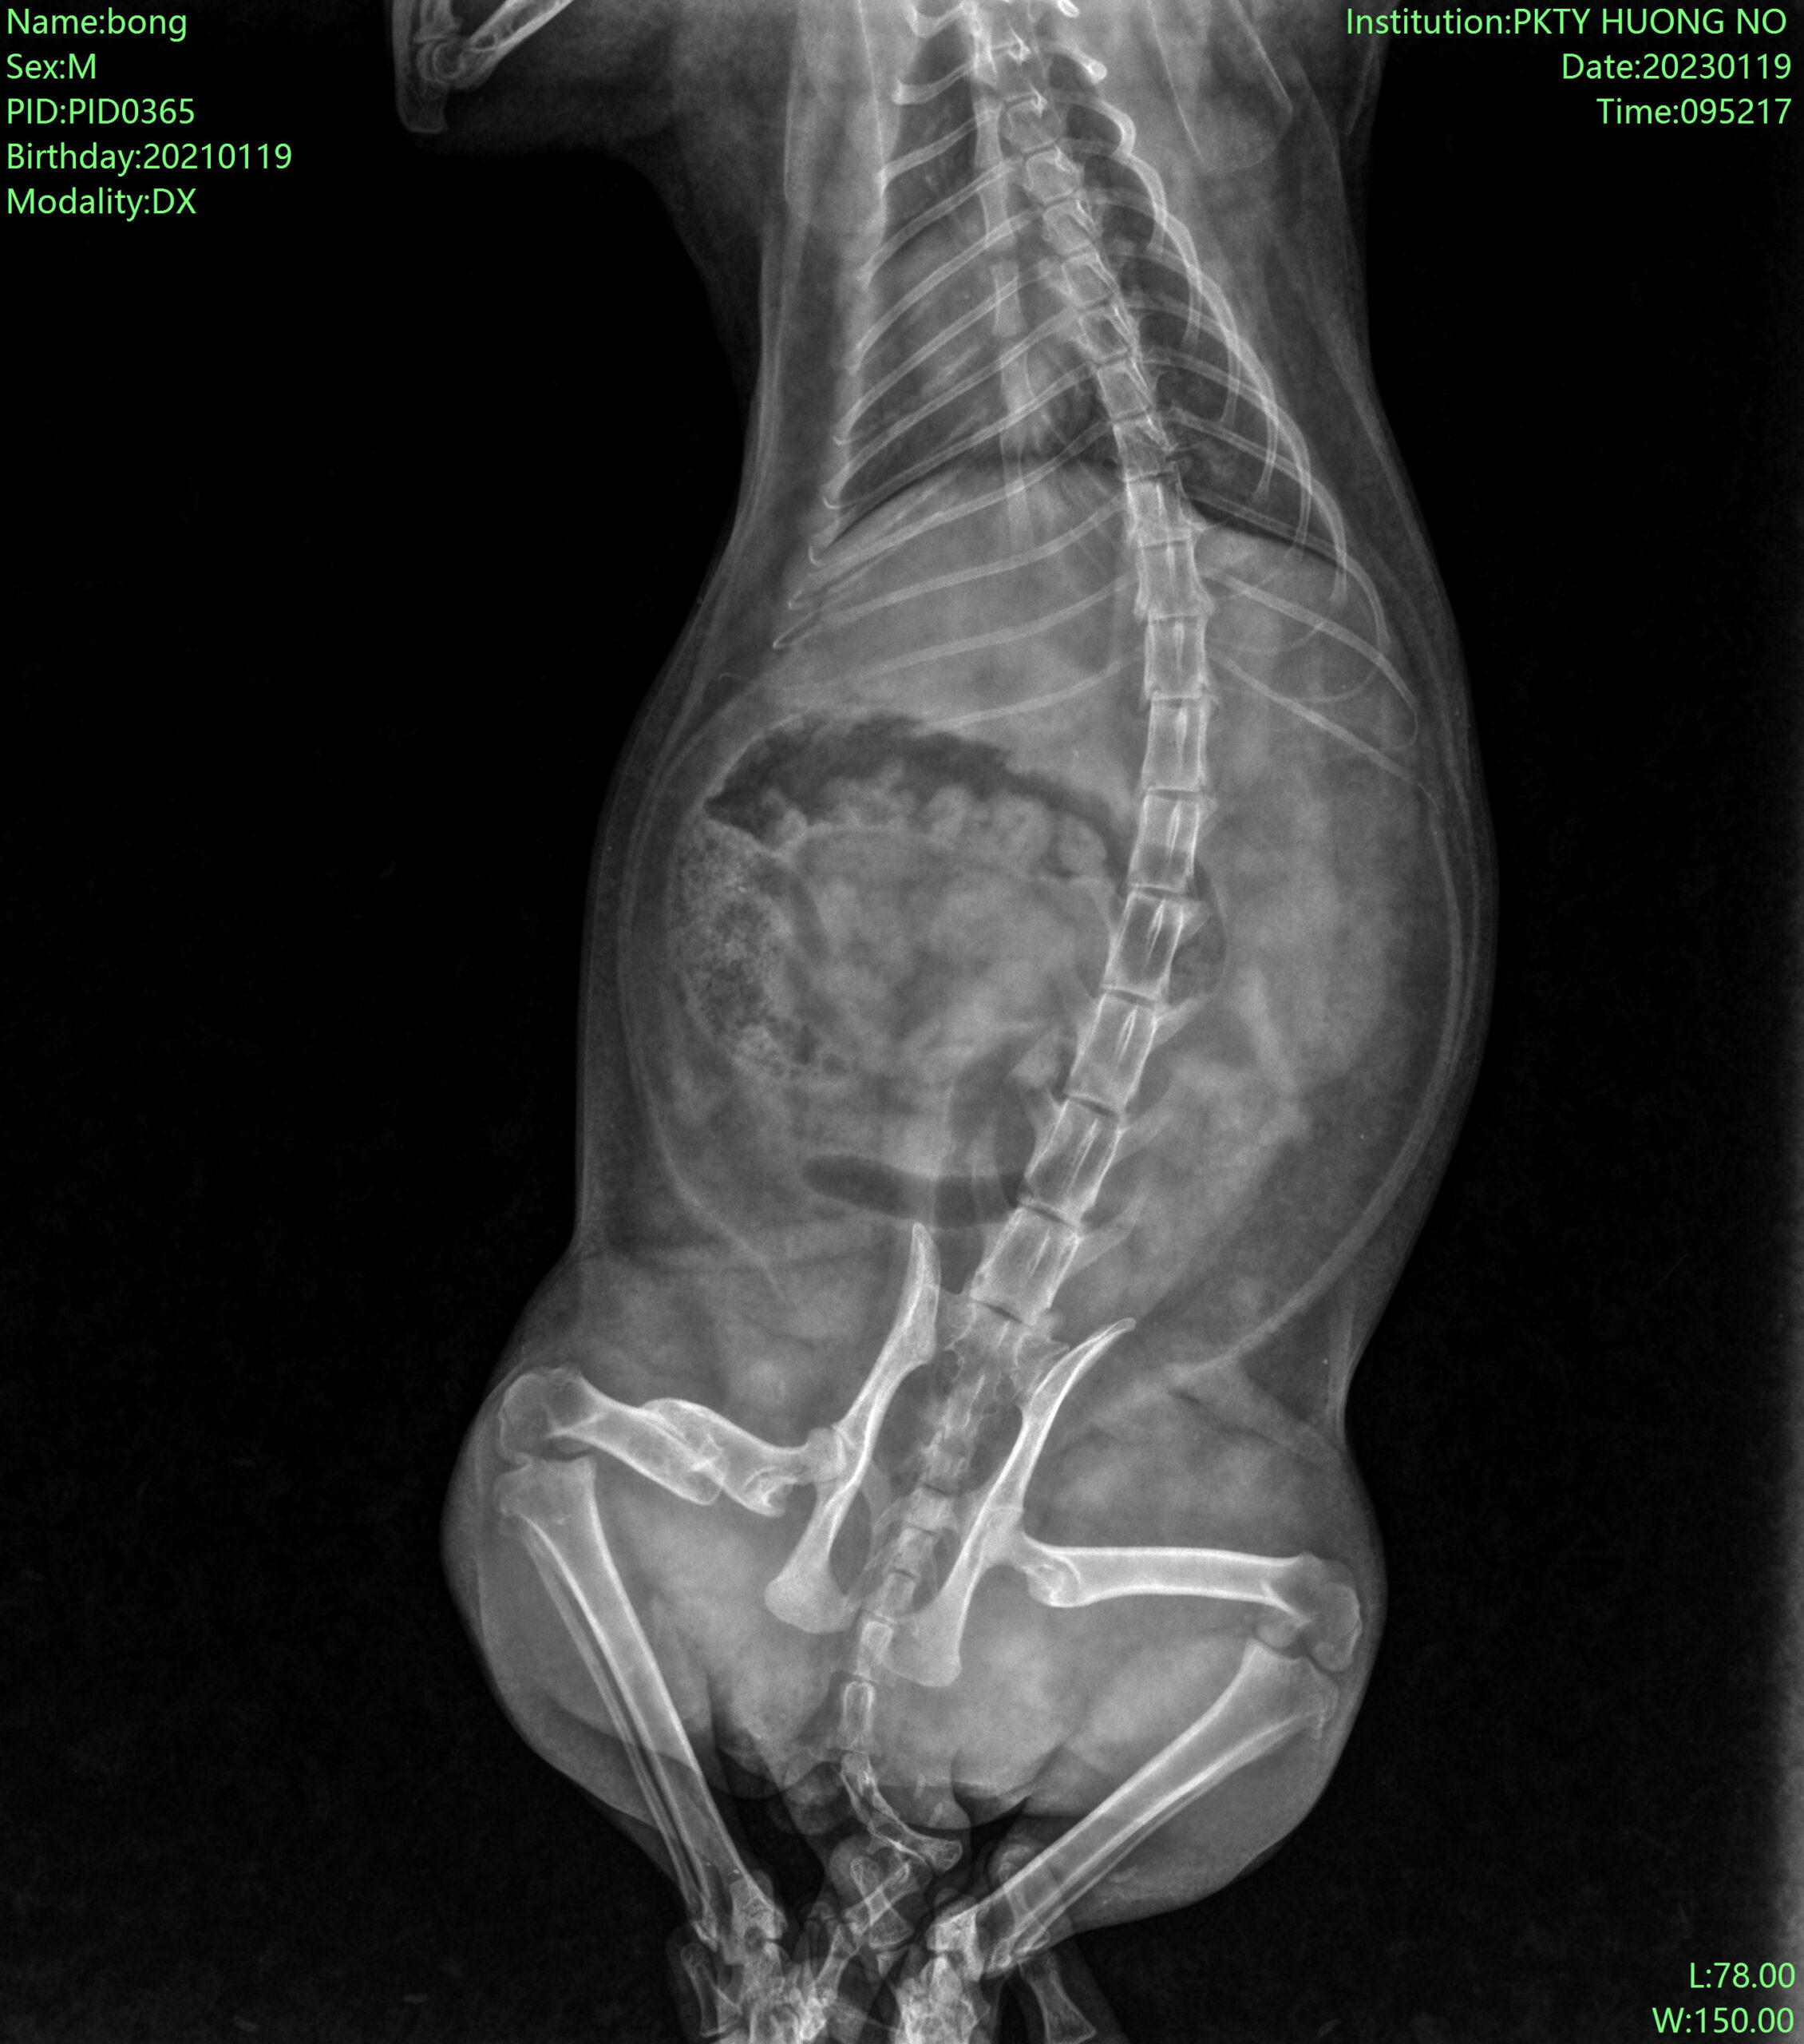

1. Ca phẫu thuật xương đùi bé cún bị tai nạn:

Trước phẫu thuật:

2. Ca ghép xương bé cún bị xe cán: